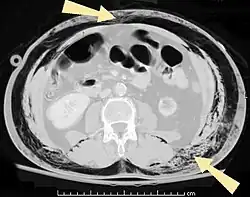

| An abdominal CT scan of a patient with subcutaneous emphysema (arrows) | |

Signs and symptoms of spontaneous subcutaneous emphysema vary based on the cause, but it is often associated with swelling of the neck and chest pain, and may also involve sore throat, neck pain, difficulty swallowing, wheezing and difficulty breathing.[5] Chest X-rays may show air in the mediastinum, the middle of the chest cavity.[5] A significant case of subcutaneous emphysema can be detected by touching the overlying skin, which will feel like tissue paper or Rice Krispies.[8] Touching the bubbles causes them to move and sometimes make a crackling noise.[9] The air bubbles, which are painless and feel like small nodules to the touch, may burst when the skin above them is palpated.[9] The tissues surrounding SCE are usually swollen. If large amounts of air leak into the tissues around the head, the face can swell considerably.[8] In cases of subcutaneous emphysema around the neck, there may be a feeling of fullness in the neck, and the sound of the voice may change.[10] If SCE is particularly extreme around the neck and chest, the swelling can interfere with breathing. The air can travel to many parts of the body, including the abdomen and limbs, because there are no separations in the fatty tissue in the skin to prevent the air from moving.[11]

Significant cases of subcutaneous emphysema are easy to diagnose because of the characteristic signs of the condition.[1] In some cases, the signs are subtle, making diagnosis more difficult.[13] Medical imaging is used to diagnose the condition or confirm a diagnosis made using clinical signs. On a chest radiograph, subcutaneous emphysema may be seen as radiolucent striations in the pattern expected from the pectoralis major muscle group. Air in the subcutaneous tissues may interfere with radiography of the chest, potentially obscuring serious conditions such as pneumothorax.[18] It can also reduce the effectiveness of chest ultrasound.[28] On the other hand, since subcutaneous emphysema may become apparent in chest X-rays before a pneumothorax does, its presence may be used to infer that of the latter injury.[13] Subcutaneous emphysema can also be seen in CT scans, with the air pockets appearing as dark areas. CT scanning is so sensitive that it commonly makes it possible to find the exact spot from which air is entering the soft tissues.[13] In 1944, M.T. Macklin and C.C. Macklin published further insights into the pathophysiology of spontaneous Macklin's Syndrome occurring as a result of a severe asthmatic attack.